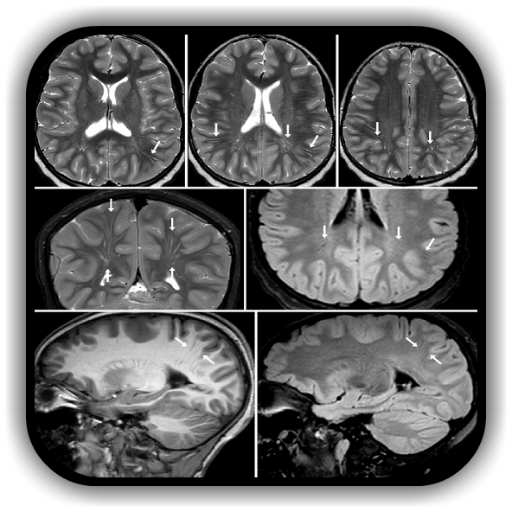

Dilared Perivaskular Ruang

Pembesaran atau Asimetri Ventrikel sisi mensimulasikan hydrocephalus

Kerbil atau Cerebellar Kehilangan kelantangan mensimulasikan hematoma subdural, hygromas, dan sista arknoid